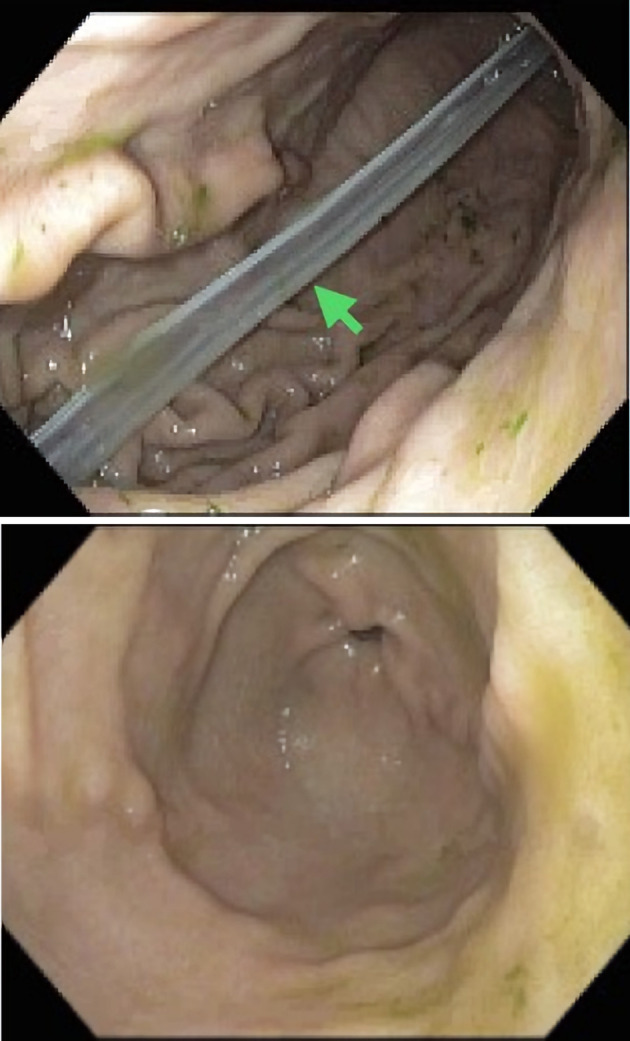

Orogastric tubes (OGTs) are frequently used to administer feeds and medications to critically ill patients. They are inserted blindly, with a low first-pass success rate and frequent benign complications. OGT fractures and ingestion are exceedingly rare, with only two cases reported to date. Herein, we describe a rare case of OGT transection and ingestion in a male patient admitted for hyperacute delirium and complicated pneumonia. The OGT remnant was retrieved using an endoscope without any complications. Clinicians must be aware of this rare but potentially catastrophic complication of OGT use. OGTs must be inspected in the same manner as endotracheal tubes to ensure patient safety.